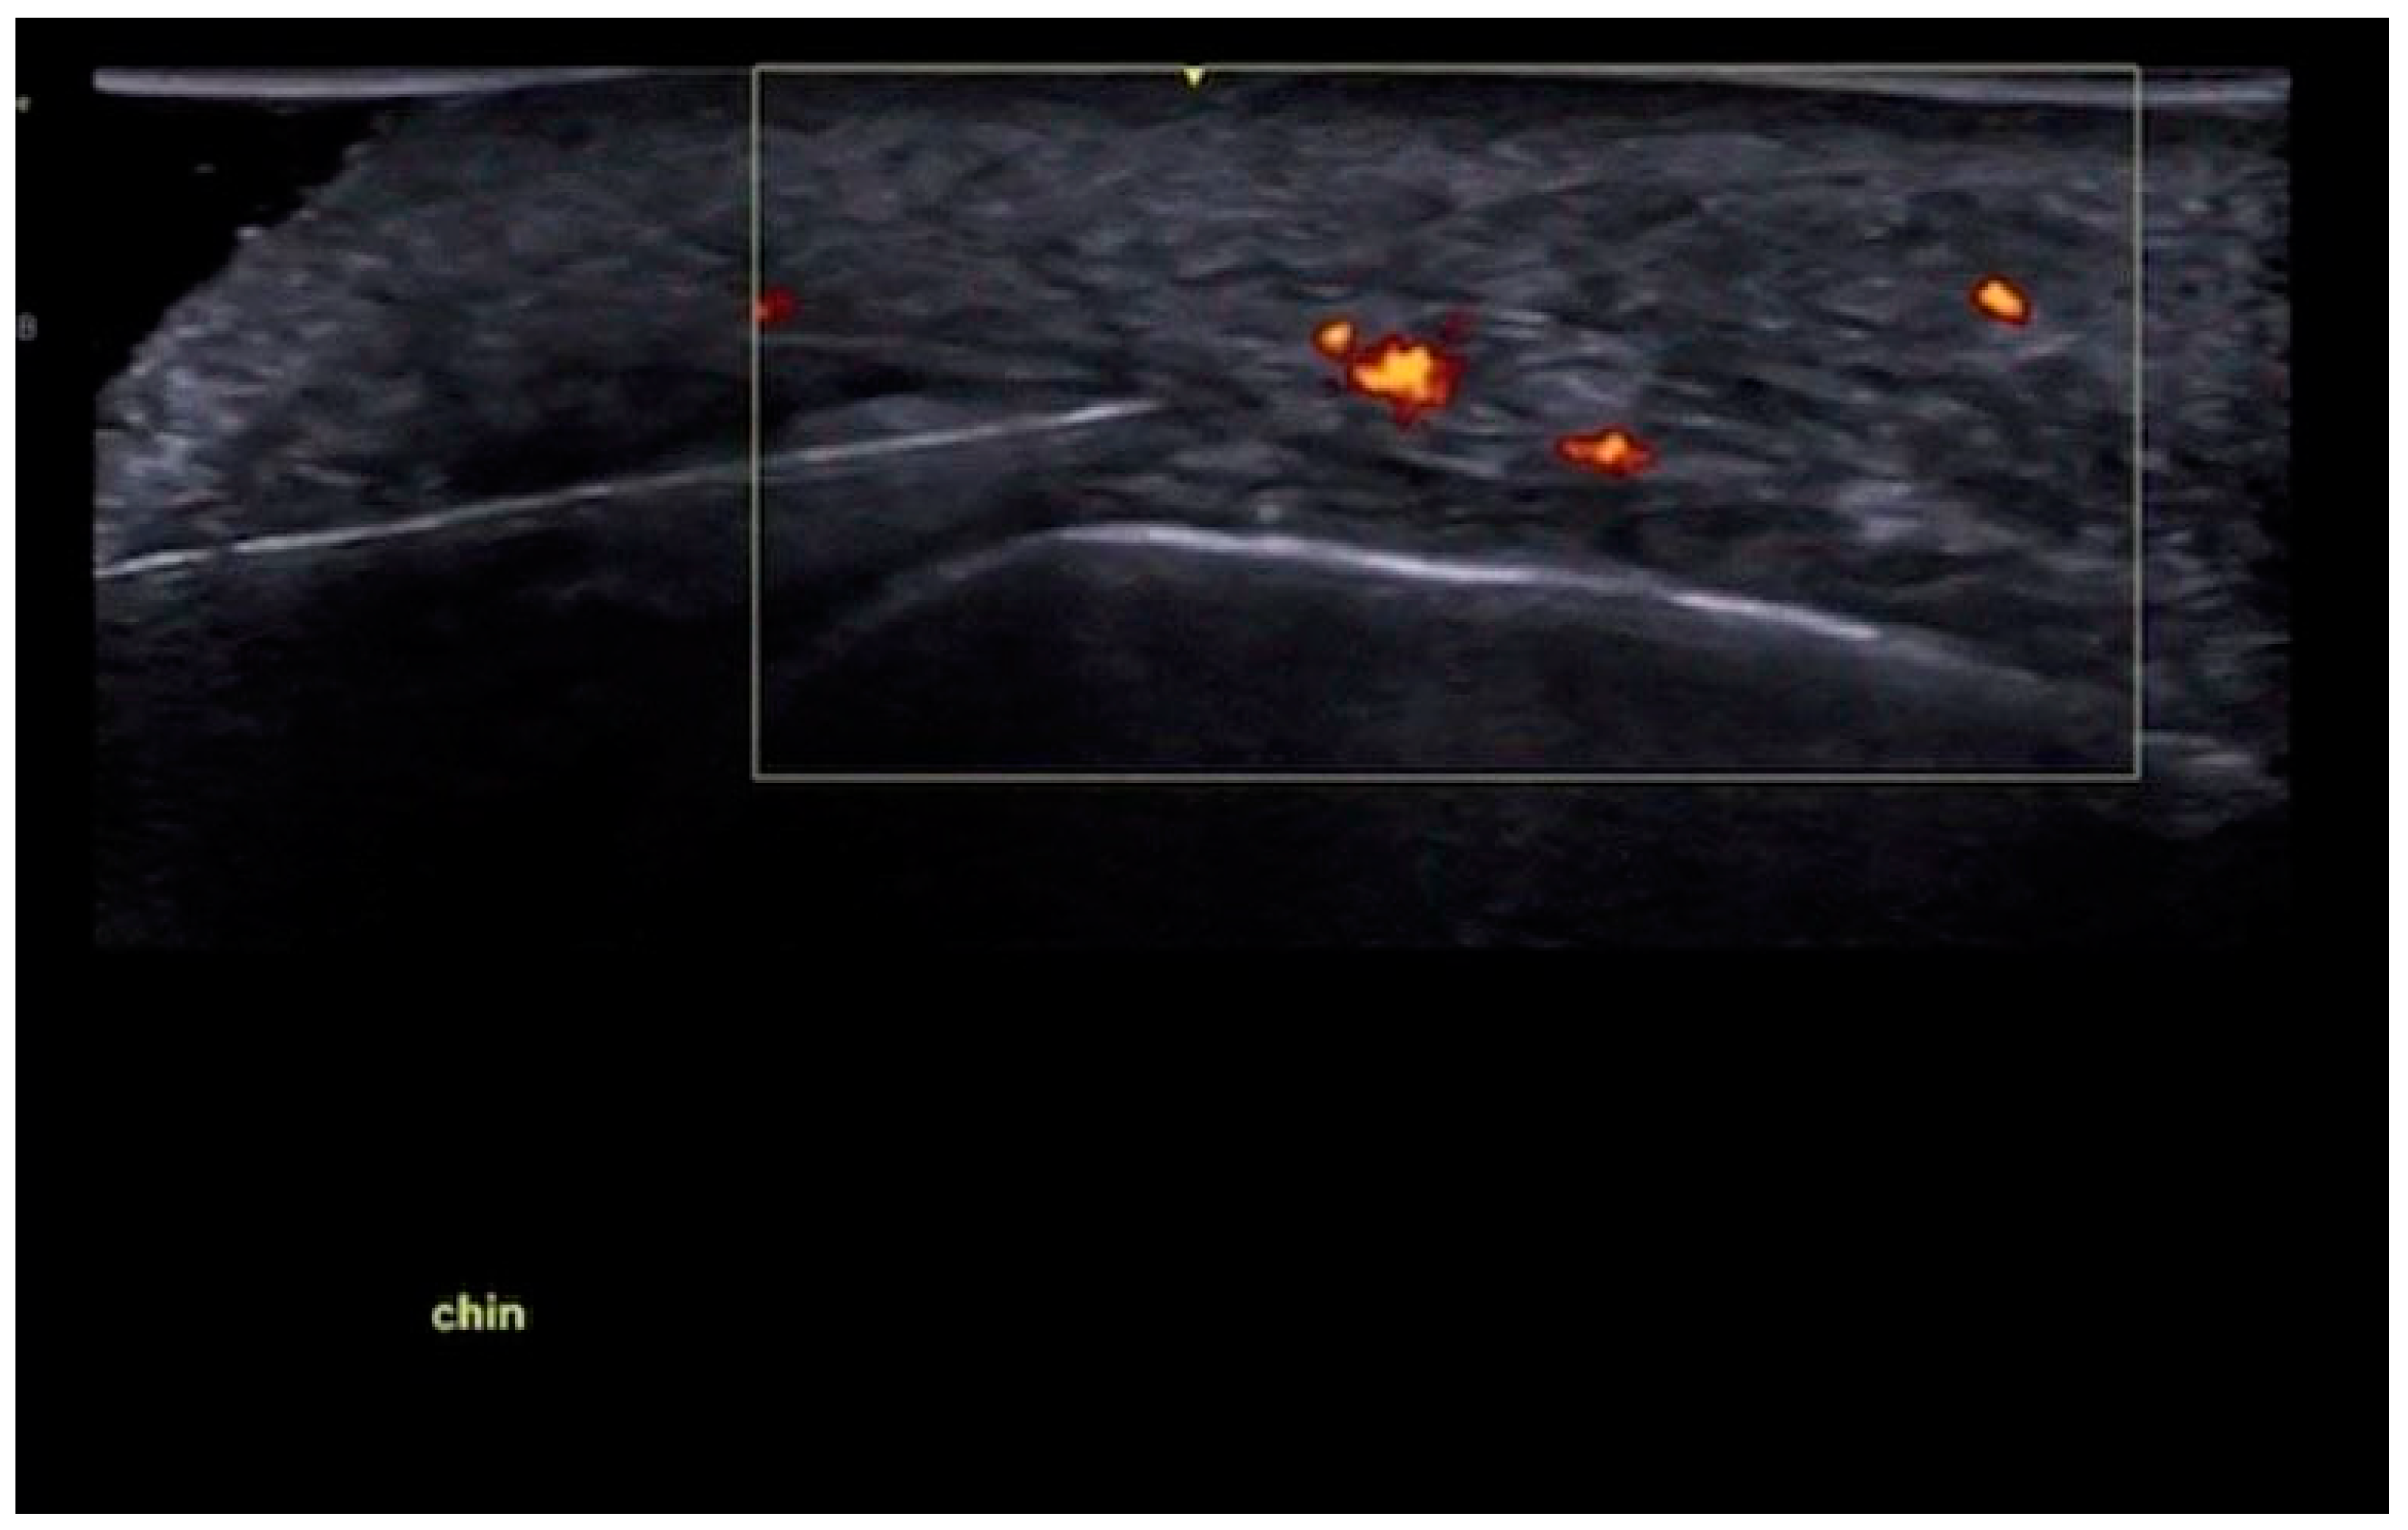

3.4.1. Sonographic Anatomy of the Chin

3.4.2. Ultrasound-Guided Filling Techniques of the Chin